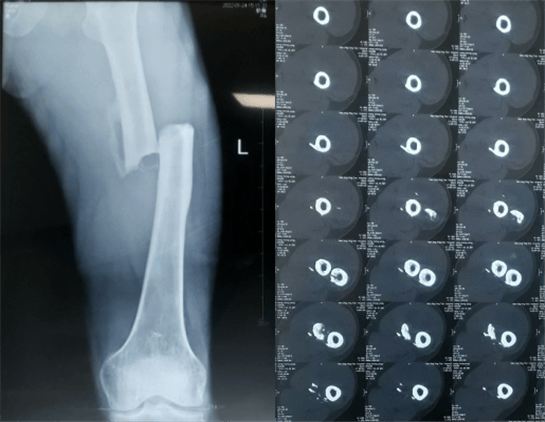

患者:男性,43歲,左股骨干骨折髓內(nèi)釘內(nèi)固定術

醫(yī)院:南京應天骨科醫(yī)院

股骨是下肢的主要負重骨,有其特殊的解剖關系,周圍肌肉發(fā)達,因此一旦股骨干骨折后如果治療不當,容易造成肌肉牽拉,導致畸形和功能障礙。治療股骨干骨折,必須遵循恢復肢體的長度及力線,無旋轉(zhuǎn),盡量行以微創(chuàng),保護骨折局部血運,促進愈合。髓內(nèi)釘對骨折的固定能夠達到較大的穩(wěn)定性和堅固性,可以減少醫(yī)源性污染,減少軟組織分離及周圍血供破壞,有利于骨折早期愈合,是治療股骨干骨折的首要治療方法。

術前檢查